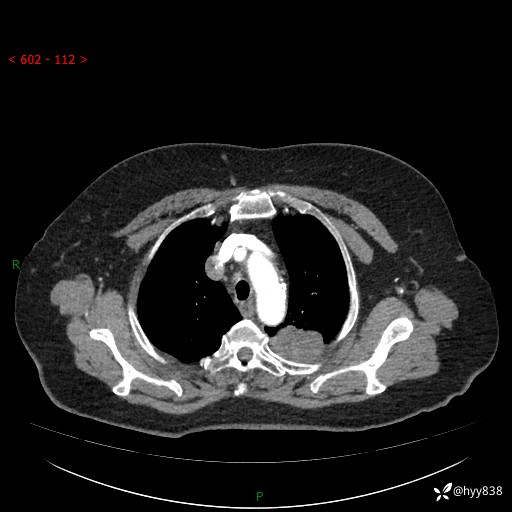

简要病史:患者于8年前体检行胸部CT检查发现左上肺结节(4mm),患者平素间断咳嗽咳痰,无心慌、胸闷、胸痛、呼吸困难、低热、盗汗,无头痛、头晕,无腹痛、腹胀等不适,未行特殊处理,定期复查。2023-09-21胸部CT示左上肺结节(2cm)较前增大,2024-02-01胸部CT示左上肺尖后段(39*32mm),左侧肺门及纵隔淋巴结增大,现患者欲求手术治疗,遂来我院就诊,以“左上肺结节”收入我科。 患者自起病以来,精神可,睡眠可,饮食可,大小便正常,体重无明显改变。

增强(动脉期+静脉期)